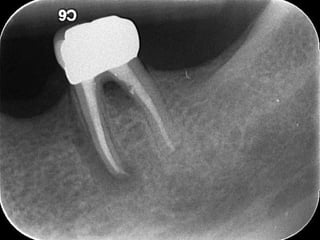

Retreatment &

Iatrogenic Errors

Tooth Related

Contended

Contraindications

Referral is usually

required

Needs experience